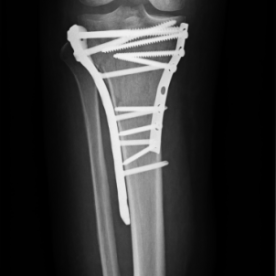

Röntgenbilder

• Knochenbrüche der oberen und unteren Extremitäten